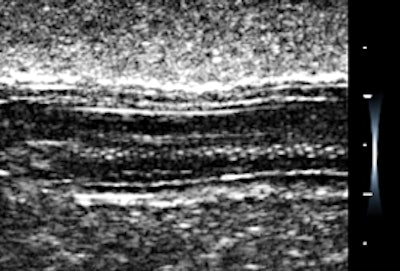

What astounded me was that the system is fully adjustable through a mini-keyboard plugged into one of the USB connectors. There is a screen overlay for all kinds of adjustment, so that you can see the results in real-time. Preferred settings are saved by depth in any of a number of folders. My experience is that once these are set, I really did not have to vary them much afterward, although I can. The display shifts from vertical to horizontal as the unit is rotated, like a smartphone, and the image is moved or magnified with finger movements. Here are some Metamucil gelatin phantom images on my first day of scanning with the linear array at 10 and 12 MHz. These are original except for cropping.

The first phantom image is of a gherkin, although I should say "cornichon," as this is a French unit. The settings were optimized for spatial resolution showing the tiny seeds along the axis.